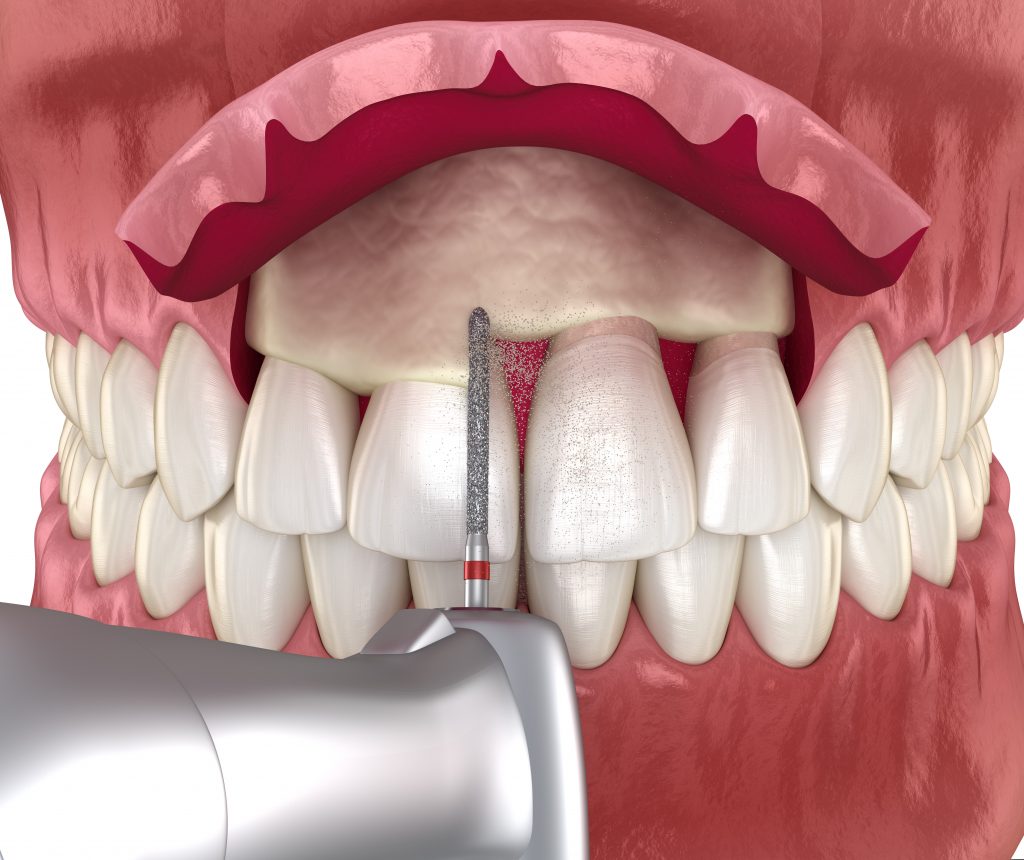

Crown lengthening treatment removes excess gum tissue from around one or more of your teeth, exposing additional tooth structure above your gumline. This may be recommended if you have a “gummy” smile or to provide better access to correct issues with decayed or broken teeth or infected gums.

During treatment, your gums are moved away from your tooth and jawbone. The bone will be smoothed, if needed, prior to reattaching the gums lower on the teeth. With more tooth structure showing above the gumline, your teeth now appear longer and your gums less prominent.